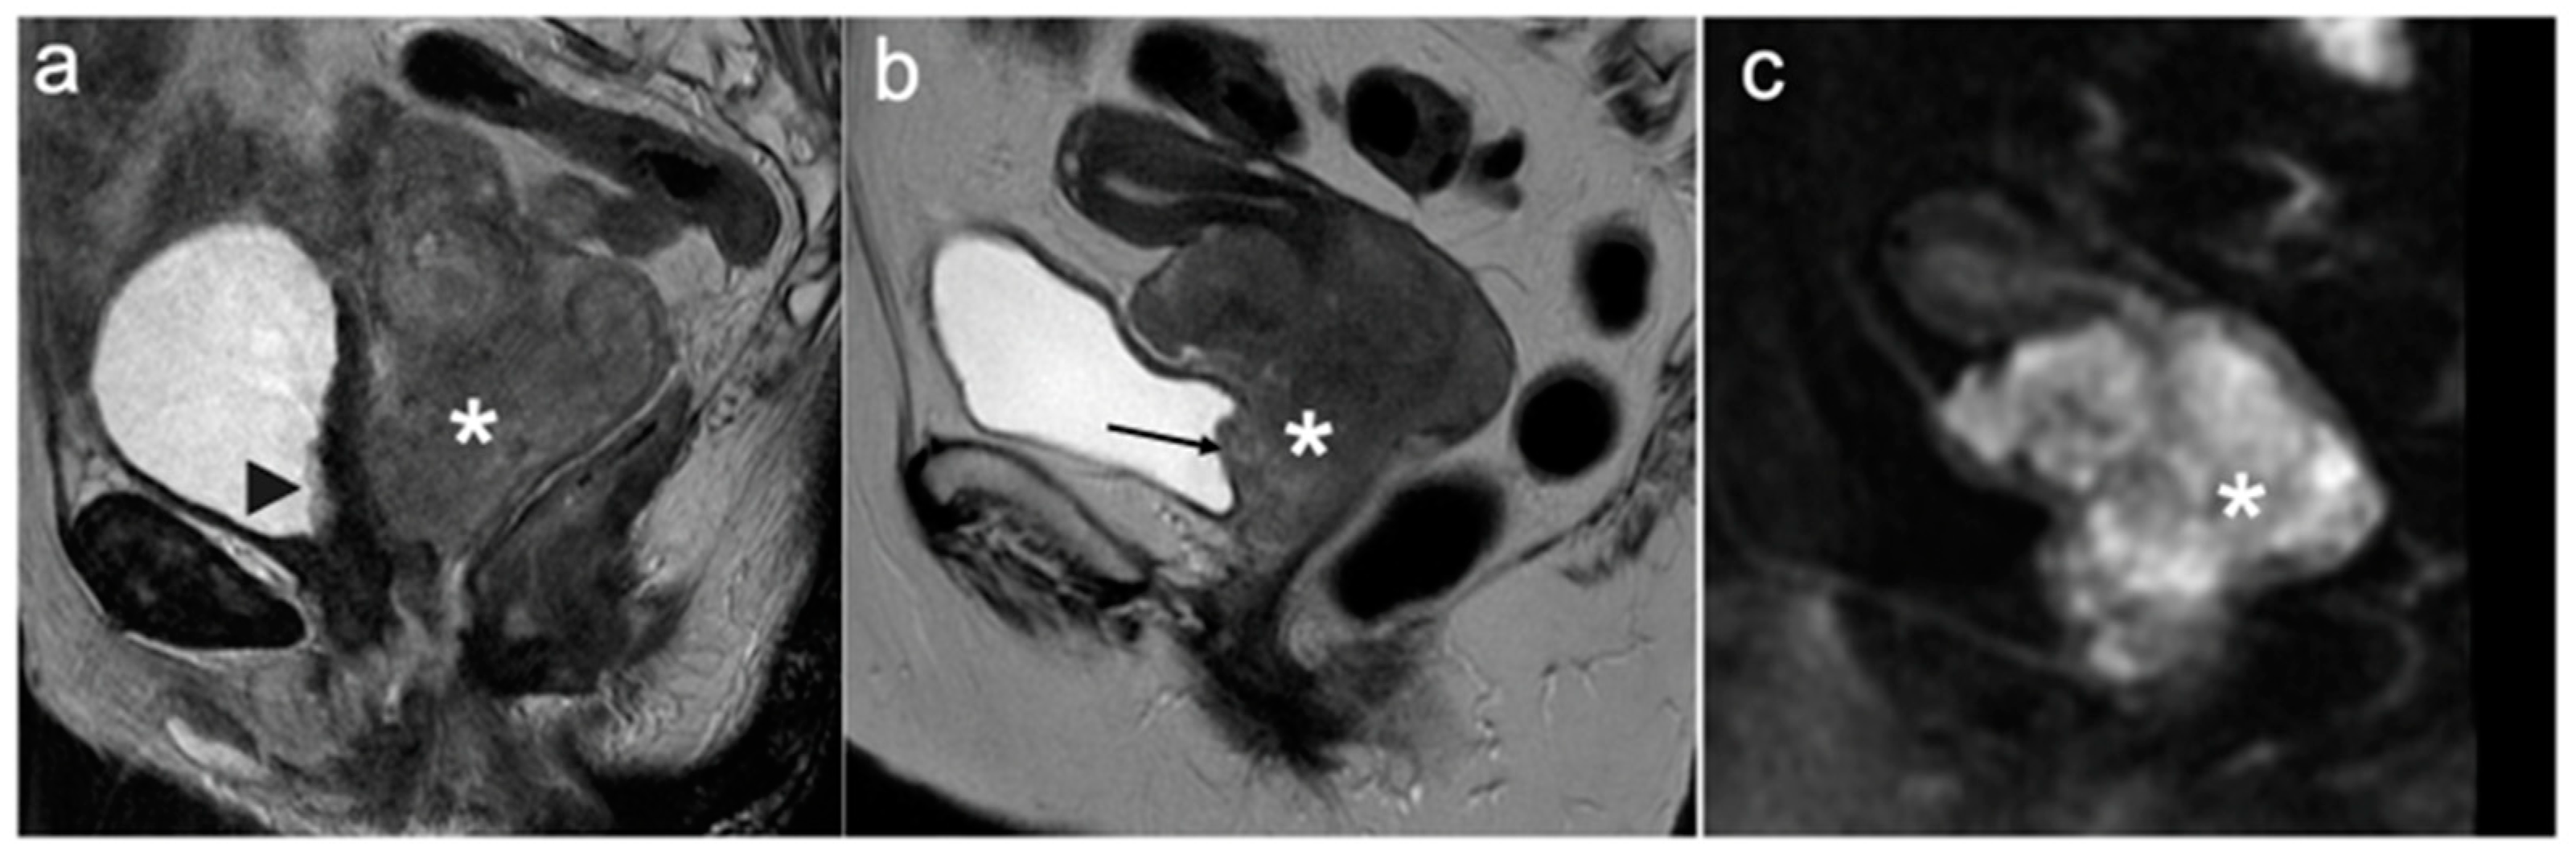

4. FIGO Stage I

5. FIGO Stage II

- McEvoy, S.H.; Nougaret, S.; Abu-Rustum, N.R.; Vargas, H.A.; Sadowski, E.A.; Menias, C.O.; Shitano, F.; Fujii, S.; Sosa, R.E.; Escalon, J.G.; et al. Fertility-sparing for young patients with gynecologic cancer: How MRI can guide patient selection prior to conservative management. Abdom. Radiol. 2017, 42, 2488–2512, Erratum in Abdom. Radiol. 2017, 42, 2966–2973. [Google Scholar]

- Halaska, M.; Robova, H.; Pluta, M.; Rob, L. The role of trachelectomy in cervical cancer. Ecancermedicalscience 2015, 9, 506. [Google Scholar] [CrossRef]

- Rockall, A.G.; Qureshi, M.; Papadopoulou, I.; Saso, S.; Butterfield, N.; Thomassin-Naggara, I.; Farthing, A.; Smith, J.R.; Bharwani, N. Role of Imaging in Fertility-sparing Treatment of Gynecologic Malignancies. Radiographics 2016, 36, 2214–2233. [Google Scholar] [CrossRef] [PubMed]

- Moro, F.; Bonanno, G.M.; Gui, B.; Scambia, G.; Testa, A.C. Imaging modalities in fertility preservation in patients with gynecologic cancers. Int. J. Gynecol. Cancer 2021, 31, 323–331. [Google Scholar] [CrossRef] [PubMed]

- Noël, P.; Dubé, M.; Plante, M.; St-Laurent, G. Early cervical carcinoma and fertility-sparing treatment options: MR imaging as a tool in patient selection and a follow-up modality. Radiographics 2014, 34, 1099–1119. [Google Scholar] [CrossRef] [PubMed]